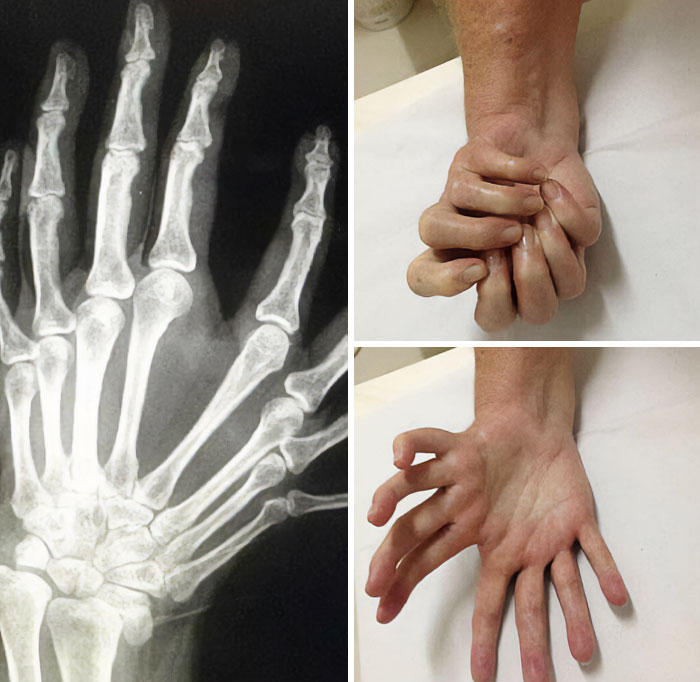

Polidactilia